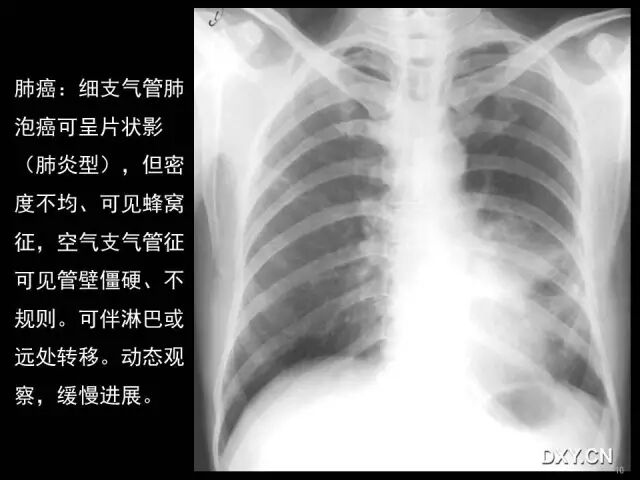

肺炎、肺癌、肺结核在影像学上的征象往往千变万化。